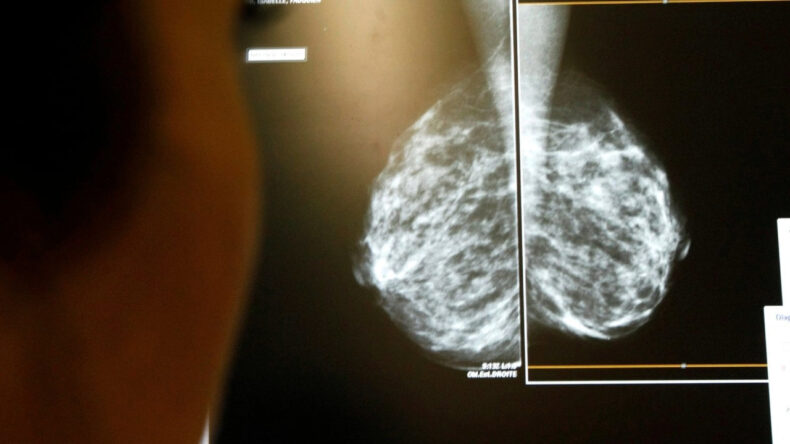

Yeni bir araştırma, meme kanseri taramalarında yapay zeka kullanımının geç teşhis olasılığını yüzde 12 oranında azalttığını ortaya koydu.

Lund Üniversitesi'nde gerçekleştirilen bu çalışma, saygın tıp dergisi The Lancet'te yayımlandı ve İsveç'te mamografi taramasına katılan 100 bin kadını inceledi.

Nisan 2021 – Aralık 2022 tarihleri arasında yapılan araştırma, katılımcıları iki gruba ayırarak yürütüldü. Bir grup, yapay zeka destekli tarama testlerinden yararlanırken, diğer grup ise iki radyoloğun geleneksel değerlendirmeleriyle değerlendirildi.

Yapay zeka sistemi, mamografi görüntülerini analiz ederek risk düzeyine göre vakaları yönlendirdi. Düşük riskli vakalar tek bir radyoloğa, yüksek riskli olanlar ise iki radyoloğun incelemesine yönlendirildi. Ayrıca yapay zeka, şüpheli alanları belirleyerek radyologlara karar verme süreçlerinde destek sağladı.

Araştırma sonuçlarına göre, meme kanseri teşhisi sonrası yıllarda yapay zeka uygulanan grupta 1000 kadında 1.55 oranında teşhis konulurken, kontrol grubunda bu oran 1000 kadında 1.76 olarak belirlendi.

Yapay zeka ile değerlendirilen grupta kanser vakalarının yüzde 81'i tarama aşamasında tespit edilirken, geleneksel yöntemle bu oran yüzde 74'te kaldı. Ayrıca, yapay zekanın kullanıldığı grupta meme kanserinin ağır alt tipleri yüzde 27 daha az görüldü.

Araştırmacılar, yapay zekanın radyologların iş yükünü azaltmada destek sağlayabileceğini ifade ederken, bu araçların sürekli izleme altında ve dikkatlice uygulanması gerektiğinin altını çizdi.